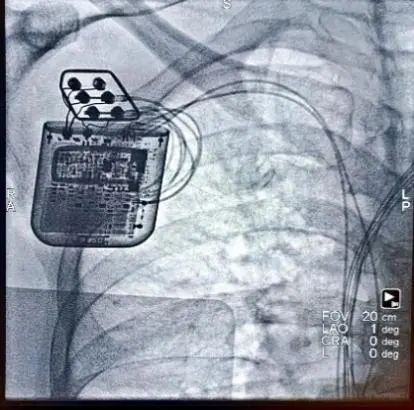

4月25日下午,由于波院长亲自指导,李述峰主任和曹威教授共同配合,术前暂时关闭CRT-D除颤功能后,右侧腋静脉路径将两根电极导线精准放置于右心室间隔面,调节至各项参数都达到最佳状态后,连接好CCM装置,经过程控设置后开始发放脉冲,心电监护仪上可清晰看到QRS不应期存在稳定的CCM电信号,随后进行CCM与CRT-D交叉感知测试,调节参数使CCM信号落入CRT-D心房通道PVAB、心室通道PVB不产生额外计数且对CRT-D形态学鉴别无影响,调节优化至患者最舒适状态,最后将装置埋入预先制作的囊袋中。手术采用局麻微创方式,全程1.5小时,具有不开胸、创伤小、恢复快、患者受益大等优势。

CRT-D程控仪标记CCM脉冲位于心房通道空白期且形态学鉴别无影响

监护仪显示CCM信号稳定发放